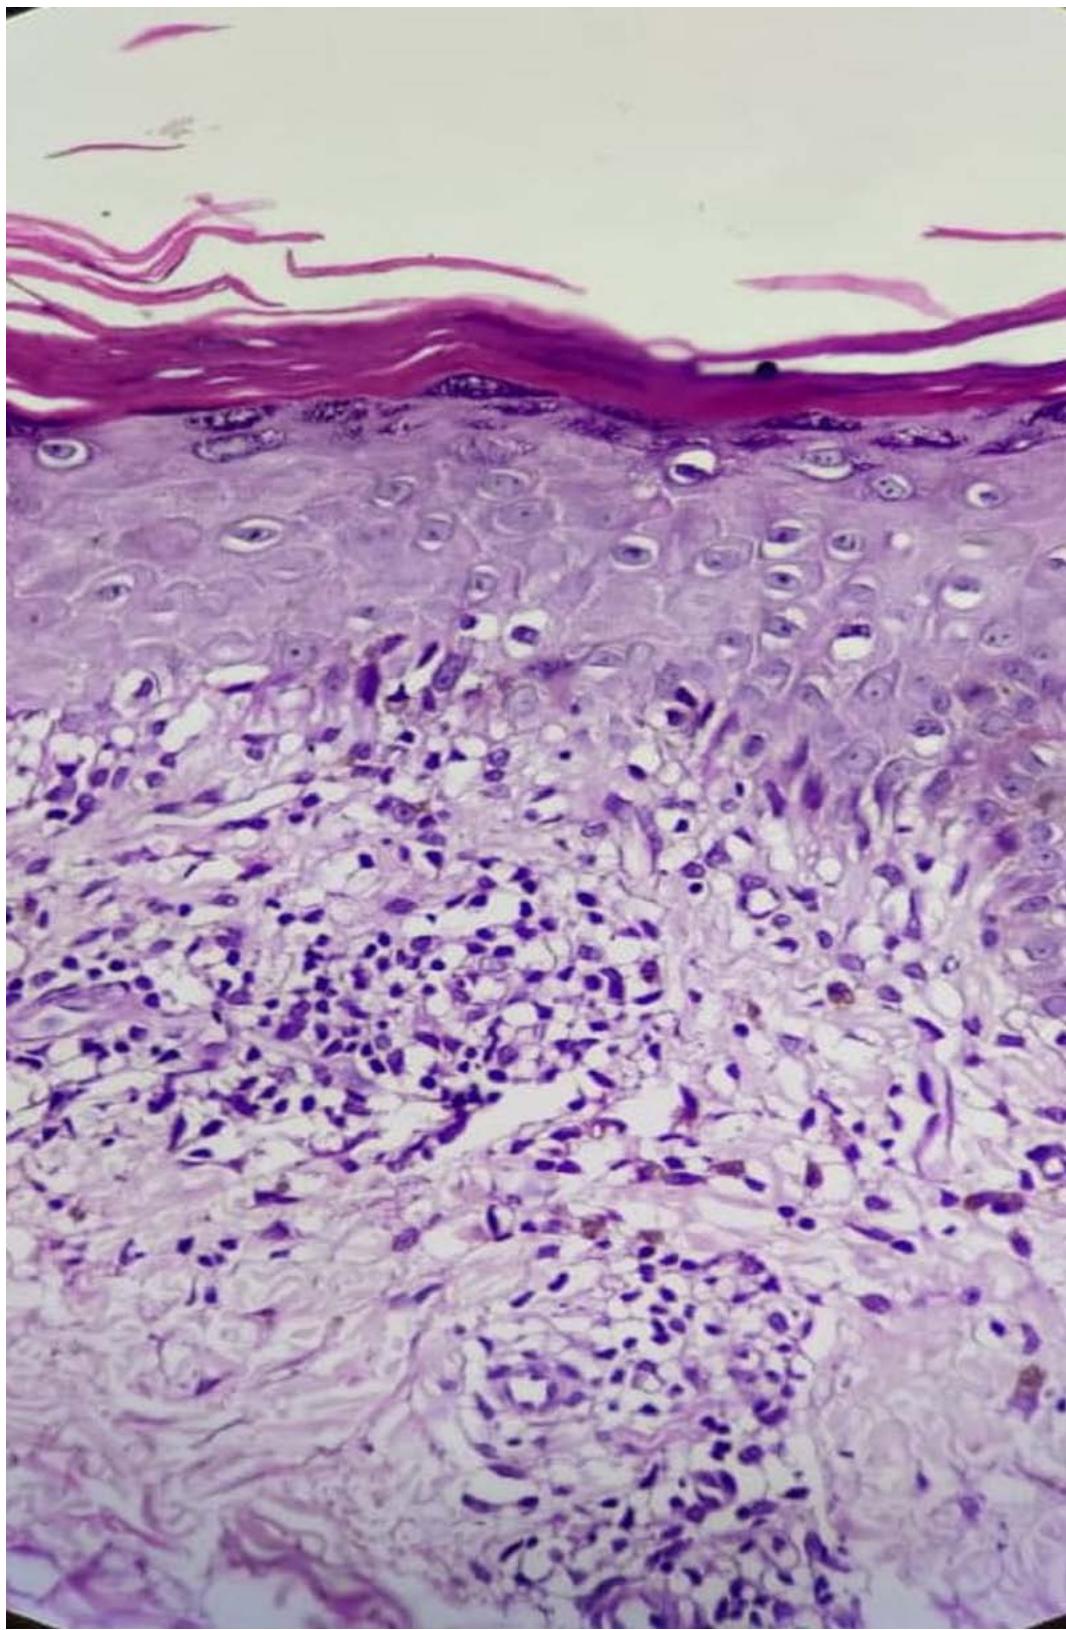

A 14-year-old female presented with multiple dark coloured, itchy lesions on legssince5 months. On examination, multiple violaceous papules to plaques of varying sizes (1cm - 5cm) were present on the extensor aspects of legs, forearm and dorsum of feet bilaterally. (Figs 1-3). Skin biopsy from the lesion showed hyperkeratosis, hypergranulosis, vacuolar degeneration of basal layer, band of dense lymphocytic inflammatory infiltrate in the papillary dermis, with perivascular histiocytic infiltrate confirming the diagnosis of lichen planus (LP) (Fig 4,5). She was started on topical corticosteroids, antihistamines and emollients. After 3 months patient had aggravation of LP with patchy hair loss over the scalp. On examination multiple, smooth alopecic patches of varying sizes, the largest being $4 \times 3 \mathrm{~cm}$, were noticed on the scalp. She was diagnosed clinically as alopecia areata (AA) (Fig 6). Investigations like complete blood count, liver function test, thyroid profile, anti-nuclear antibody, rheumatoid arthritis factor, C-reactive protein, ESR, VDRL, HBV, HCV, urine microscopy were normal. In view of progressing lesions of LP and AA, she was started on oral mini pulse therapy-betamethasone 5 mg twice weekly and was advised for follow-up. Good response was noticed by four weeks withresolution of LP and regrowth of hair over few patches.

Figure 4: Photomicrograph showing hyperkeratosis, parakeratosis, hypergranulosis, band of dense lymphocytic inflammatory infiltrate, histiocytes admixed with congested blood vessels, along with periadnexal inflammatory infiltrate. (H & E, x 40).